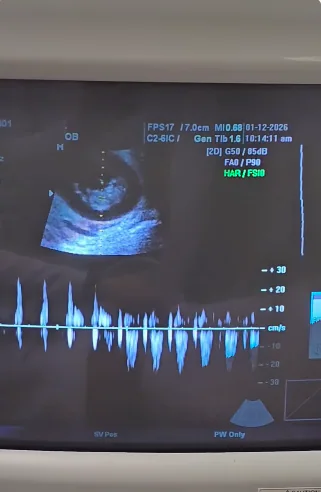

Robyn Brown, a Filipino-American hurdler who plays for Team Philippines in Physical: Asia, has revealed that she and her spouse, Alejandro Castillo, are expecting their first child.

Robyn shared a collection of videos showing their pregnancy announcement on her Instagram page.

On her Instagram page, Robyn posted a number of videos showing their pregnancy announcement.